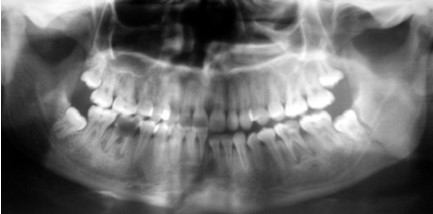

Fig 4: Panoramic radiograph of bilateral angle fracture (sever displacement of the left , , side not associated with third molar)

Only two cases without lower third molar in the fracture site represented sever displacement of the angle fracture (figure 4).